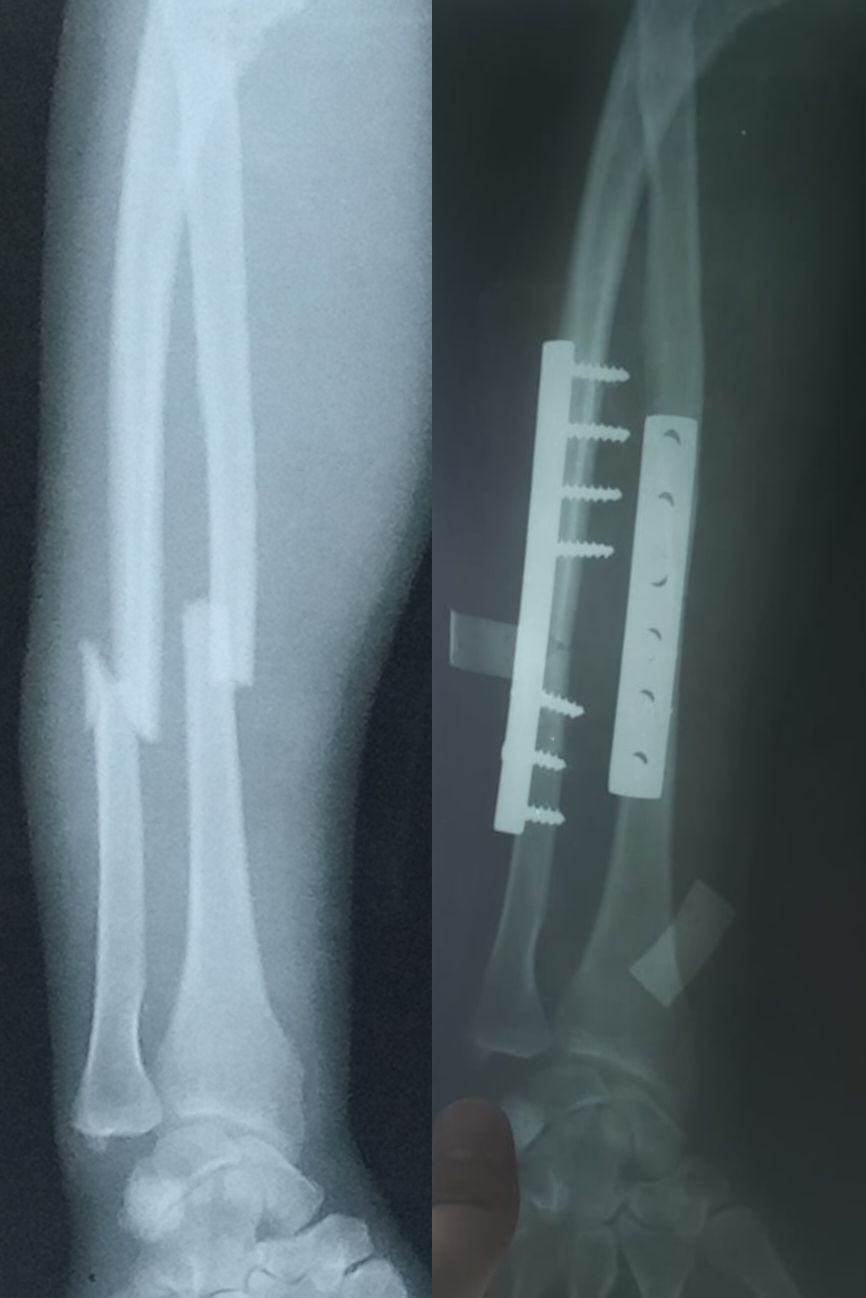

Fx Radius & Ulna shaft

ORIF e DCP done

Trauma

Fracture

Orthopedics